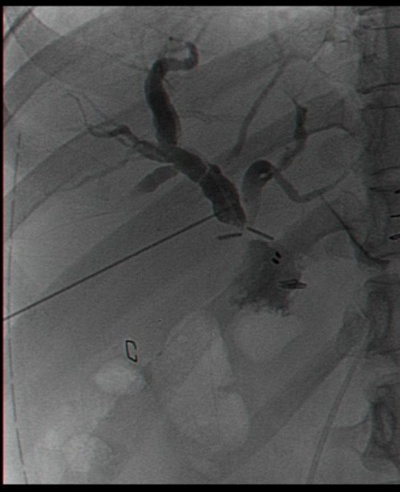

יש המבצעים בשלב זיהוי הצינור המרה צילום דרכו לזיהוי אנטומי ולהדגמה של אבנים בכולדוכוס. כיס המרה מורם ומופרד מבסיסו כלפי מעלה בעזרת דיאתרמיה-מספריים או וו (Hook) ממיטת כיס המרה שעל הכבד (איור 11.8). לאחר ניתוקו מוצא כיס המרה דרך אחד הפתחים בדופן הבטן, בפתח שדרכו מוחדרת המצלמה או בפתח העליון (איור 7.8).

עניין הכולאנגיוגרפיה התוך-ניתוחית מצביע על חוסר אחדות דעים בגישתם של המנתחים השונים. היו מנתחים שביצעו כולאנגיוגרפיה תוך-ניתוחית באופן שגרתי, ואילו אחרים שעשו זאת רק כשיש חשד סביר לאבנים בדרכי המרה (אנזימי כבד מופרעים, דרכי מרה מורחבות או בנוכחות אבנים בדרכי המרה בבדיקת אולטרה-סאונד). כיום ההוריה העיקרית לצילום דרכי המרה היא לצורך הדגמה אנטומית של דרכי המרה בעלי אנטומיה לא-ברורה של דרכי המרה.

בחולים שלהם סימנים לאבנים בדרכי המרה, כגון בחולים שאובחנו בהם התרחבות של דרכי המרה באולטרה-סאונד, ביוכימיה של צהבת חסימתית שלא חלפה לגמרי או שערכי הפוספטאזה בסיסית נותרו גבוהים, או בחולים שנתגלתה בהם עדות לאבנים בדרכי המרה באחד מאמצעי ההדמיה, יש להמליץ על ביצוע ERCP לפני ניתוח. בחולים שבהם אין לבצע את הבדיקה בגלל בעיות טכניות, אפשר לבצע כולאנגיוגרפיה תוך-ניתוחית על-ידי החדרת צנתר לצינור כיס המרה דרך אחד המחדרים ולבצע צילום של דרכי המרה דרכו. אם מתגלים אבנים, יש מנתחים המנסים להוציאן בעזרת סלים (Baskets) דרך צינור כיס המרה או לדחוף אותן דרך הפפילה בזמן הלפרוסקופיה.